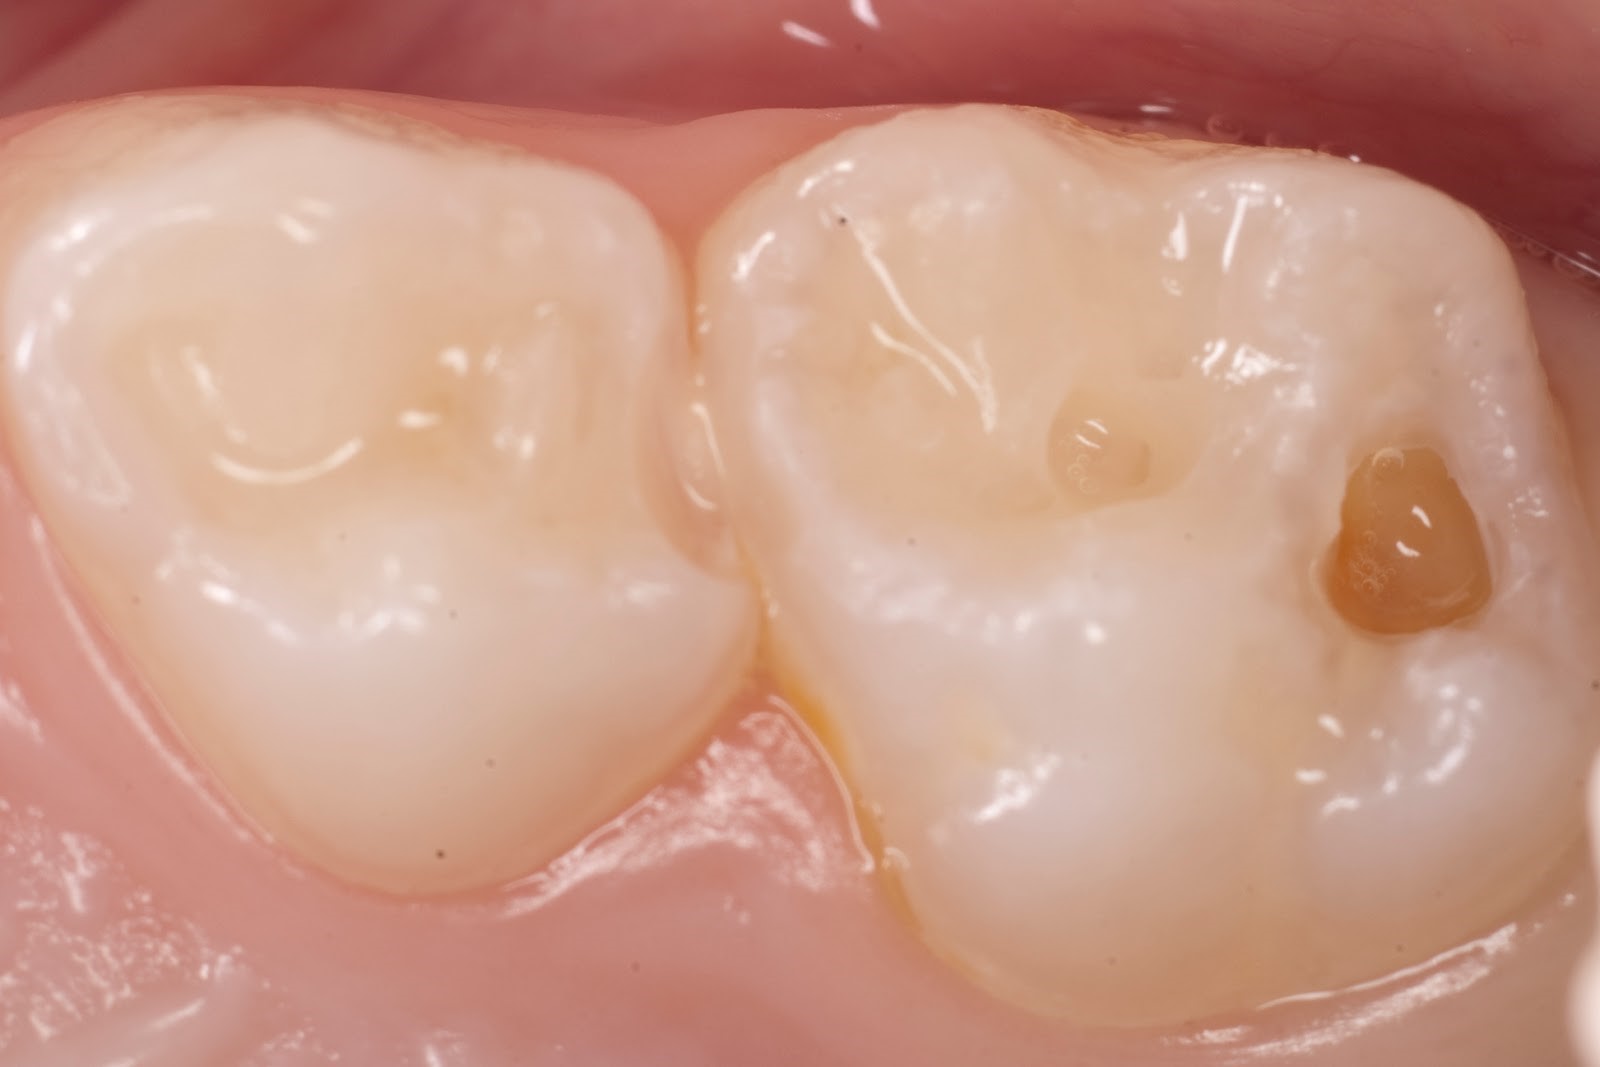

Средний кариес молочных зубов

На фотографии показан средний кариес молочных зубов. Кариес — процесс разрушения зуба. Средняя стадия которая доставляет уже больше неприятностей пациенту. При среднем кариес поражается и эмаль, и слой денты.